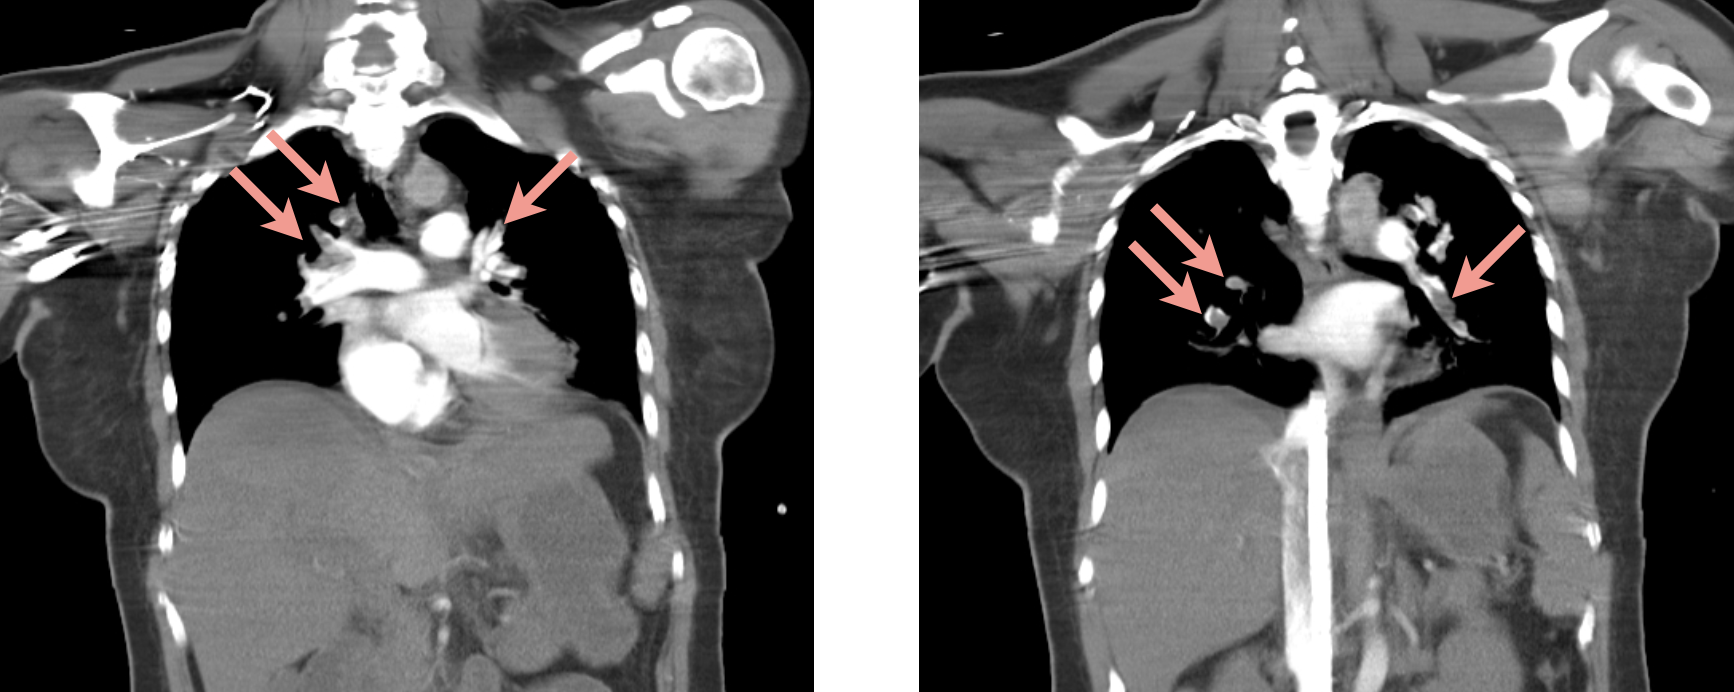

去了CT room

大片雙側肺栓塞

我覺得診斷不是重點。

因為有蠻多證據顯示就是肺栓塞: